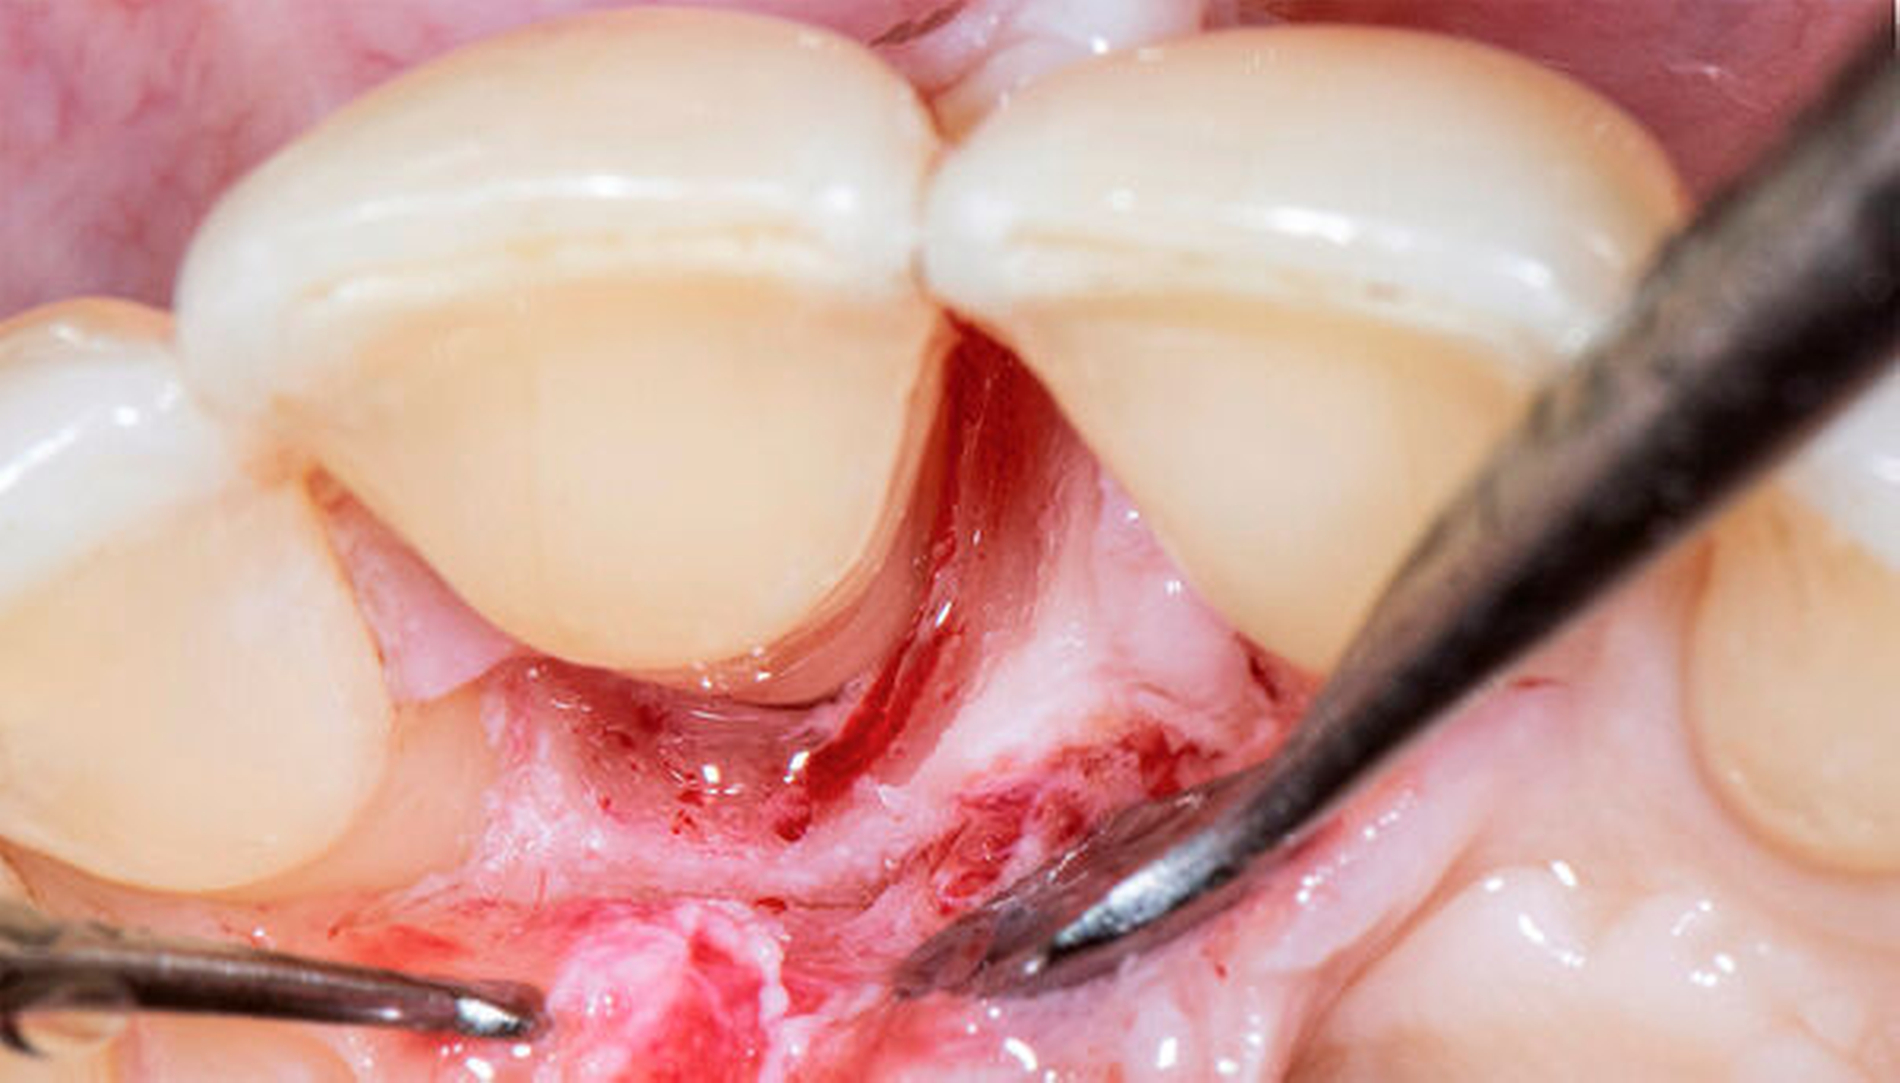

Neue Trends und Entwicklungen in der modernen Oralchirurgie gehen allerdings in Richtung sehr feiner Skalpellklingen, die extrem kleine chirurgische Zugänge ermöglichen und noch weniger invasive mikrochirurgische Techniken erlauben [Rebele et al., 2014; Zuhr et al., 2018]. Auf dieser Grundlage lässt sich vermuten, dass die mikrochirurgischen Instrumente und Nahtmaterialien in der oralen Mikrochirurgie in Zukunft wieder kleiner werden könnten und deshalb auch wieder höhere Vergrößerungsfaktoren für die zu ihrer Anwendung erforderlichen Sehhilfen notwendig werden (Abbildungen 5 bis 16). So wie es in anderen mikrochirurgischen Fachdisziplinen bereits heute Realität ist, könnten vor diesem Hintergrund auch zukünftige Generationen dentaler Operationsmikroskope im Hinblick auf Flexibilität, Workflow und Anwenderfreundlichkeit verbessert und auf diese Weise wieder einen festen Platz in einer oralchirurgisch tätigen Praxis einnehmen. Eine gute Perspektive könnten auch innovative Lupensysteme darstellen, die bereits heute mit Vergrößerungsfaktoren von 9.0x bis 10.0x angefertigt werden können.